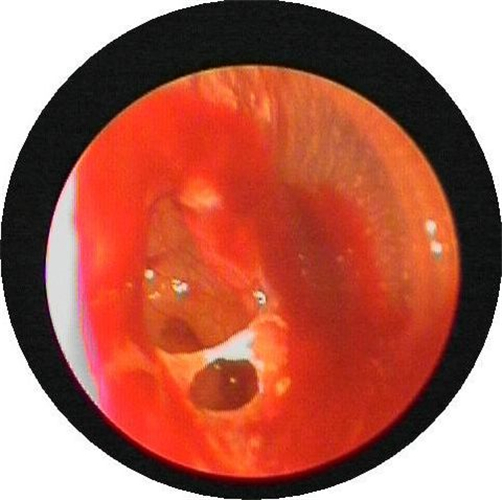

左耳鼓膜穿孔